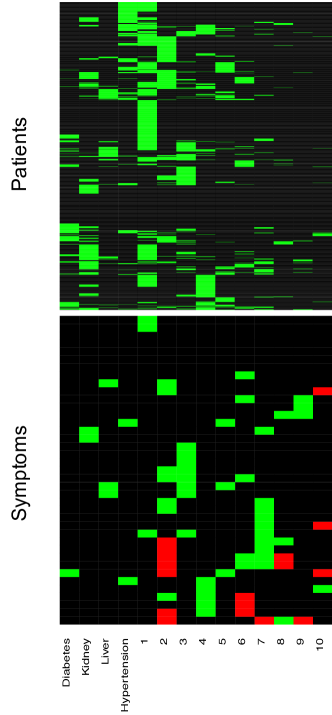

We ran the MCMC algorithm described in Section 4 for 50,000 iterations. The first half of the iterations are discarded as burn-in and posterior samples are retained at every 5th iteration thereafter. Goodness-of-fit and MCMC convergence diagnostics show adequate fit and no evidence for lack of convergence (Supplementary Material B). Posterior probabilities for the number of latent diseases are and , respectively, i.e., the maximum a posteriori (MAP) estimate is . This includes the 4 a priori known diseases as well as 10 newly discovered latent diseases.

Conditional on , the posterior estimates of the PD and SD models are shown as a heatmap in Figure 7 with green, black and red cells representing 1, 0 and -1, respectively. The nature of the figure as a single heatmap with two blocks, for PD and SD, respectively, highlights again the nature of the model as a “double” feature allocation with matching subsets of patients and symptoms. The model allocates both, patients and symptoms, to latent diseases. As mentioned before, DFA can also be interpreted as an edge-labeled network. We show the same results as in the heatmap as a bipartite graph in Figure 8(a). The full inferred model would be a tripartite network, as in the bottom portion of Figure 4. However, we omit the patient nodes in Figure 8(a) , lest the figure would be overwhelmed by the patient nodes. Instead, we summarize the patient-disease relationships by specifying the font size of the disease node (triangle, purple font) proportional to the number of linked patients. Latent diseases are labeled by numbers and a priori known diseases are labeled by name. Symptoms are shown in black font, with lines showing the links to diseases. Dashed lines are symptom-disease relationships that are inferred from the data whereas solid lines are fixed by prior knowledge. Black lines indicate that symptoms are binary. Red (blue) lines indicate suppression (enhancement) relative to the normal range. Line widths are proportional to the posterior probabilities of edge inclusion.

We identify additional 10 latent diseases with prevalence of 493, 218, 192, 174, 114, 82, 64, 24, 15, and 15 patients. Some of the latent diseases are quite interesting. Latent disease 1 is lipid disorder, associated with high total cholesterol (TC), triglycerides and low density lipoprotein (LDL). Cholesterol is an organic molecule carried by lipoproteins. LDL is one type of such lipoproteins, commonly referred to as “bad” cholesterol. At normal levels, TC and LDL are essential substances for the body. However, high levels of TC and LDL put patients at increased risk for developing heart disease and stroke. Triglycerides are a type of fat found in the blood which are produced by the body from excessive carbohydrates and fats. Like cholesterol, triglycerides are essential to life at normal levels. However, a high level is associated with an increased chance for heart disease.

Latent disease 3 can be characterized as thrombocytopenia-like disease which causes low count of platelets, decreased plateletcrit (PCT) and coefficient of variation of platelet distribution (PDW-CV), and increased mean platelet volume (MPV). Patients with low platelets may not be able to stop bleeding after injury. In more serious cases, patients may bleed internally which is a life-threatening condition.

Latent disease 4 is a polycythemia-like disease, associated with elevated mean corpuscular hemoglobin concentration (MCHC), hemoglobin, erythrocytes and hematocrit (HCT). These symptoms match exactly the symptoms of polycythemia, a disease that gives rise to an increased level of circulating red blood cells in the bloodstream. Polycythemia can be caused intrinsically by abnormalities in red blood cell production or by external factors such as chronic heart diseases.

Interestingly, like latent disease 4, latent disease 6 is also related to hemoglobin, erythrocytes and HCT. However, it is linked with a decrease in these levels; hence we refer to the disease as anemia.

Latent disease 7 suggests bacterial infection with increased leukocytes, granulocytes (GRA) and heart rate, and decreased monocytes (MON) and lymphocytes (LYM). The immune system, specifically the bone marrow, produces more GRA and leukocytes to fight a bacterial infection. As a result, the relative abundance of MON and LYM decreases.

Relatedly, latent disease 8 may be caused by viral infection. Viruses can disrupt the function of bone marrow which leads to low levels of leukocytes and GRA, and high levels of LYM.

Latent disease 9 is related to allergy with abnormal basophil, GRA and LYM.

Latent disease 10 suggests that a small group of patients may have malnutrition, which is linked with low blood glucose and anemia-like symptoms such as low corpuscular volume (MCV) and corpuscular hemoglobin (MCH).

We remark that although there are clear interpretations for most latent diseases found by DFA, latent diseases 2 and 5 cannot easily be interpreted as specific diseases. Latent disease 2 is associated with 12 symptoms, which is likely beyond the number of symptoms of any single disease. Most of the symptoms, such as platelets, leukocytes and lymphocytes, are due to a weak immune system. Considering the elderly population of this dataset, aging could be a reasonable cause. Decreased heart rate and low glucose level can also be explained by aging. Latent disease 5 is linked with elevated systolic blood pressure and glucose. While those two symptoms may not be simultaneously linked to the same disease, their co-appearance should not be too surprising because the co-existence of hypertension and diabetes (to which blood pressure and glucose are known to be linked) is quite common (De Boer et al. , , 2017).